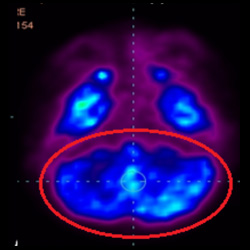

細(xì)胞治療后,藍(lán)色和黑色區(qū)域減少,并且看到更活躍的區(qū)域。這表明損傷減少并改善了大腦功能。

這證明細(xì)胞療法是治療腦癱兒童安全有效的方法。細(xì)胞療法可以更新大腦損傷的核心,并且可以通過 PET CT 掃描來監(jiān)測大腦的改善情況。這些細(xì)胞療法與標(biāo)準(zhǔn)治療一起促進(jìn)腦癱兒童的生長和改善。